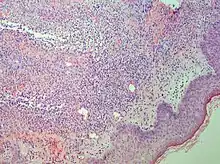

| Urticaria, lymphocyte predominant | Perivascular location. Mast cells are relatively sparse, potentially demonstrated with special stains, preferably tryptase stain. Extravasated erythrocytes are present in about 50% of the cases. No vasculitis.[14] |  Dermal edema [solid arrows in (A,B)] and a sparse superficial predominantly perivascular and interstitial infiltrate of lymphocytes and eosinophils without signs of vasculitis (dashed arrow).[15] Dermal edema [solid arrows in (A,B)] and a sparse superficial predominantly perivascular and interstitial infiltrate of lymphocytes and eosinophils without signs of vasculitis (dashed arrow).[15] |

Lymphoeosinophilic infiltrate

| Urticaria, lymphocyte predominant | Perivascular location. Mast cells are relatively sparse, potentially demonstrated with special stains, preferably tryptase stain. Extravasated erythrocytes are present in about 50% of the cases. No vasculitis.[14] |  Dermal edema (solid arrows) and a sparse superficial predominantly perivascular and interstitial infiltrate of lymphocytes and eosinophils (dashed arrow) Dermal edema (solid arrows) and a sparse superficial predominantly perivascular and interstitial infiltrate of lymphocytes and eosinophils (dashed arrow) |